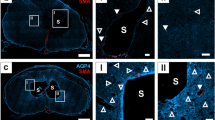

Spinal cord edema contributes to the pathophysiological mechanisms underlying spinal cord injury (SCI) and is associated with functional recovery after SCI. Early myelotomy may be a promising surgical intervention for reducing SCI-induced edema. However, it remains unclear whether myelotomy can reduce SCI-induced edema. In addition, aquaporin-4 (AQP4) and aquaporin-9 (AQP9) have important roles in the regulation of water homeostasis. Here, we aimed to determine the effects of myelotomy on AQP4 and AQP9 expression and spinal cord edema in a rat model of moderate SCI.

Rats were randomly assigned to three groups: the sham control group (n=22) receiving laminectomy alone; the contusion group (n=44) receiving laminectomy plus contusion; and the myelotomy group (n=44) receiving laminectomy plus contusion followed by myelotomy at 24 h. Functional recovery was estimated by the open-field and inclined plane tests. Spinal cord edema was determined by measuring the water content. The expression of AQP4 and AQP9 was determined by western blot.

Compared with the contusion group, myelotomy significantly improved the Basso, Beattie and Bresnahan scores in the open-field test and resulted in a higher mean angle value in the incline plane test. Myelotomy significantly reduced SCI-induced edema at 4 and 6 days after SCI, which was accompanied by downregulation of AQP4 and AQP9 expression.

Myelotomy improves locomotor function, reduces edema in rats with SCI and is associated with decreased expression of AQP4 and AQP9.